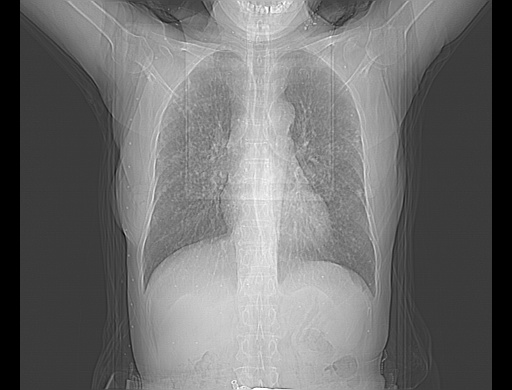

患者女性,72岁,慢性咳嗽3月余,曾抗炎治疗无效果,最近抗结核治疗约半月余,症状缓解。

ct示两肺粟粒状病灶,以两肺上叶尖后段及下叶背段分布为主;首先考虑结核。请战友们分析。

考虑 1 弥漫性泛细支气管炎, 2 结核不除外/.  有小叶中心结节 和 树芽征!!

两肺内病灶呈小结节状和树芽状,纵膈的肿大的淋巴结密度不均匀,并见有钙化,考虑为两肺结核可能更大些。

两肺内病灶呈小结节状和树芽状,纵膈的肿大的淋巴结密度不均匀,并见有钙化,多形态病灶,考虑为两肺结核,肝内考虑小囊肿。

病灶以结节为主,大部分边界清楚,分布不均,病灶形态较单一,偶见空泡征,纵膈淋巴结肿大钙化,无结核中毒症状考虑 感染性病变【真菌类可能性大】,细支气管肺泡癌。其他待排

片子很好,质量很高,两侧肺门淋巴结肿大并有钙化,两肺弥漫病灶,首先考虑tb并播散,但年龄大了呀(72岁)小细胞肺癌不能除外,如果是肺癌也没什么大的治疗了,建议正规抗结核治疗后复查